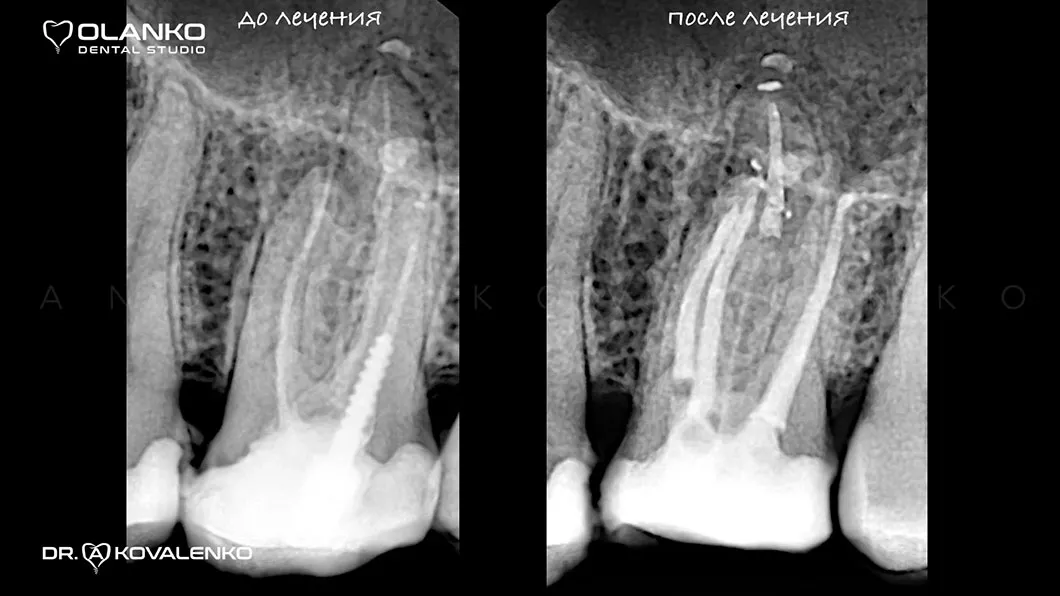

ВІДЕО ЛІКУВАННЯ КОРЕНЕВИХ КАНАЛІВ ЗУБА ПІД МІКРОСКОПОМ ТА ПОДАЛЬШИМ ВІДНОВЛЕННЯ ЗУБА КЕРАМІЧНОЮ КОРОНКОЮ

до

після

На сьогоднішній день, лікування зубів з використанням мікроскопу — це золотий стандарт світової стоматологічної практики. Складна система кореневих каналів має дуже малий діаметр та індивідуальну анатомію, тому лікар, який працює без збільшення, майже на дотик, не може якісно їх пролікувати.

Важливою перевагою Olanko dental studio (Оланко) м. Бровари є виконання всіх етапів лікування кореневих каналів тільки під контролем операційного дентального мікроскопу!

Для лікування простих клінічних випадків, як правило, потрібен всього один візит 1,5-2,5 години.

Складні випадки переліковування кореневих каналів, каналів зі складною анатомією, вимагають 2-3 візитів.

Ми маємо величезний клінічний досвід лікування зубів зі складною анатомією (викривленими, склерозованими каналами), а також повторного переліковування каналів з кістою, гранульомами, зламаними інструментами, з подальшими відмінними результатами загоєння хронічних запалень.